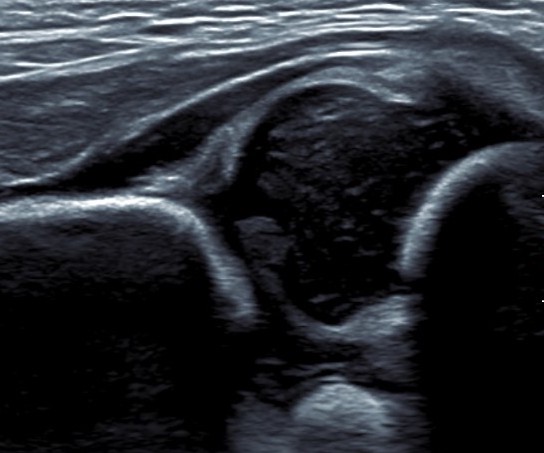

Dislocated hip on ultrasound